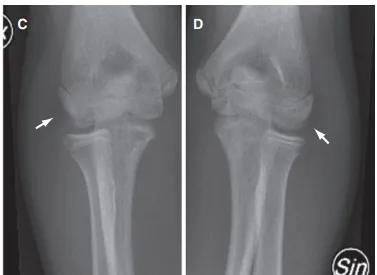

剥脱性骨软骨炎是软骨和软骨下骨与周围组织分离,主要影响膝关节、踝关节和肘关节,涉及骨骼发育紊乱,不成比例的生长和骨骼变形(图3)。研究人员对一个五代遗传性剥脱性骨软骨炎家族进行了全基因组连锁分析后,发现Aggrecan蛋白G3结构域发生了一个错义突变p.V2303M。将相关G3结构域变体与多种细胞外基质蛋白重组表达后,使用Biacore进行相互作用分析。

图3 14岁患病男孩的关节脱落情况X片图像